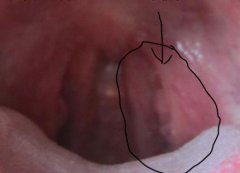

一、尖锐湿疣激光治疗是一种最常见的治疗方法之一:在医学上激光治疗是皮肤性病科,治疗尖锐湿疣最常用的方法。激光治疗的特点是见效快,在治疗的当时,疣体即可脱落。常用的是二氧化碳激光,烧灼疣体,一般1次即可使疣体脱落。

二、最普遍的一种方法是冷冻疗法这种治疗尖锐湿疣效果非常好:在生活上中冷冻疗法是一种皮肤科常用的治疗方法,主要通过以二氧化碳干冰冷冻皮肤病损来进行治疗,使皮肤损害局部水肿、坏死,以达到治疗的目的。